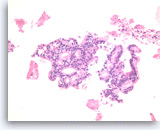

Ductal adenocarcinoma #1,

Pancreas FNA, Direct Smear.

The aspirates show single and clusters of malignant epithelial cells. The clusters are three-dimensional with overlapped nuclei. A few histiocytes are seen in the background.

20X